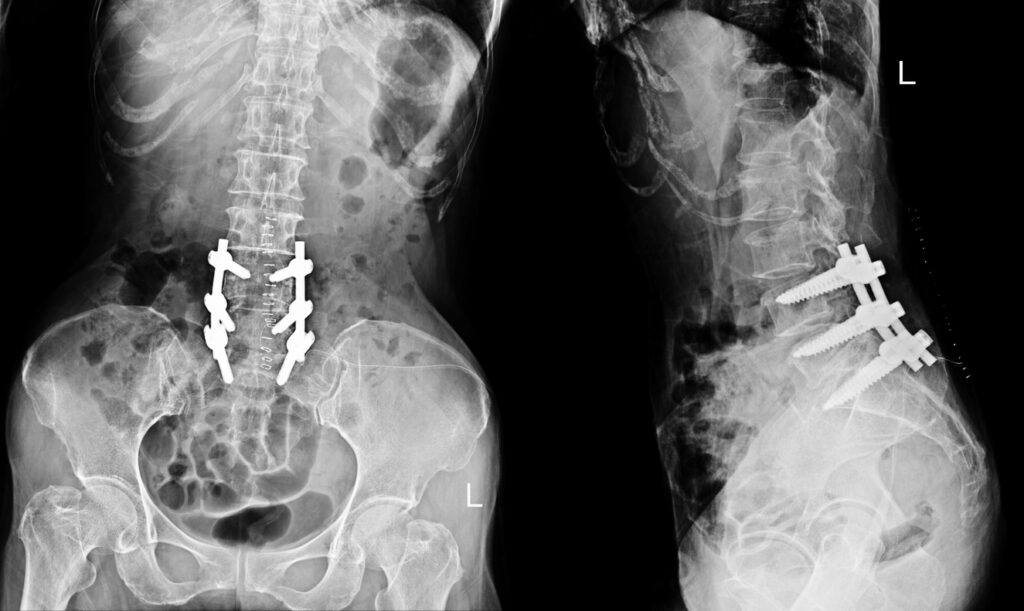

During surgery, the surgeon typically places a bone graft (natural or synthetic) between the vertebrae. Over time, this graft acts as a bridge, encouraging the vertebrae to fuse. Specialised implants such as screws, rods, or plates may also be used to hold the spine in position while the fusion takes place.

4. Instrumentation: Metal rods and screws may be used to secure the spine and enhance stability during the healing process.